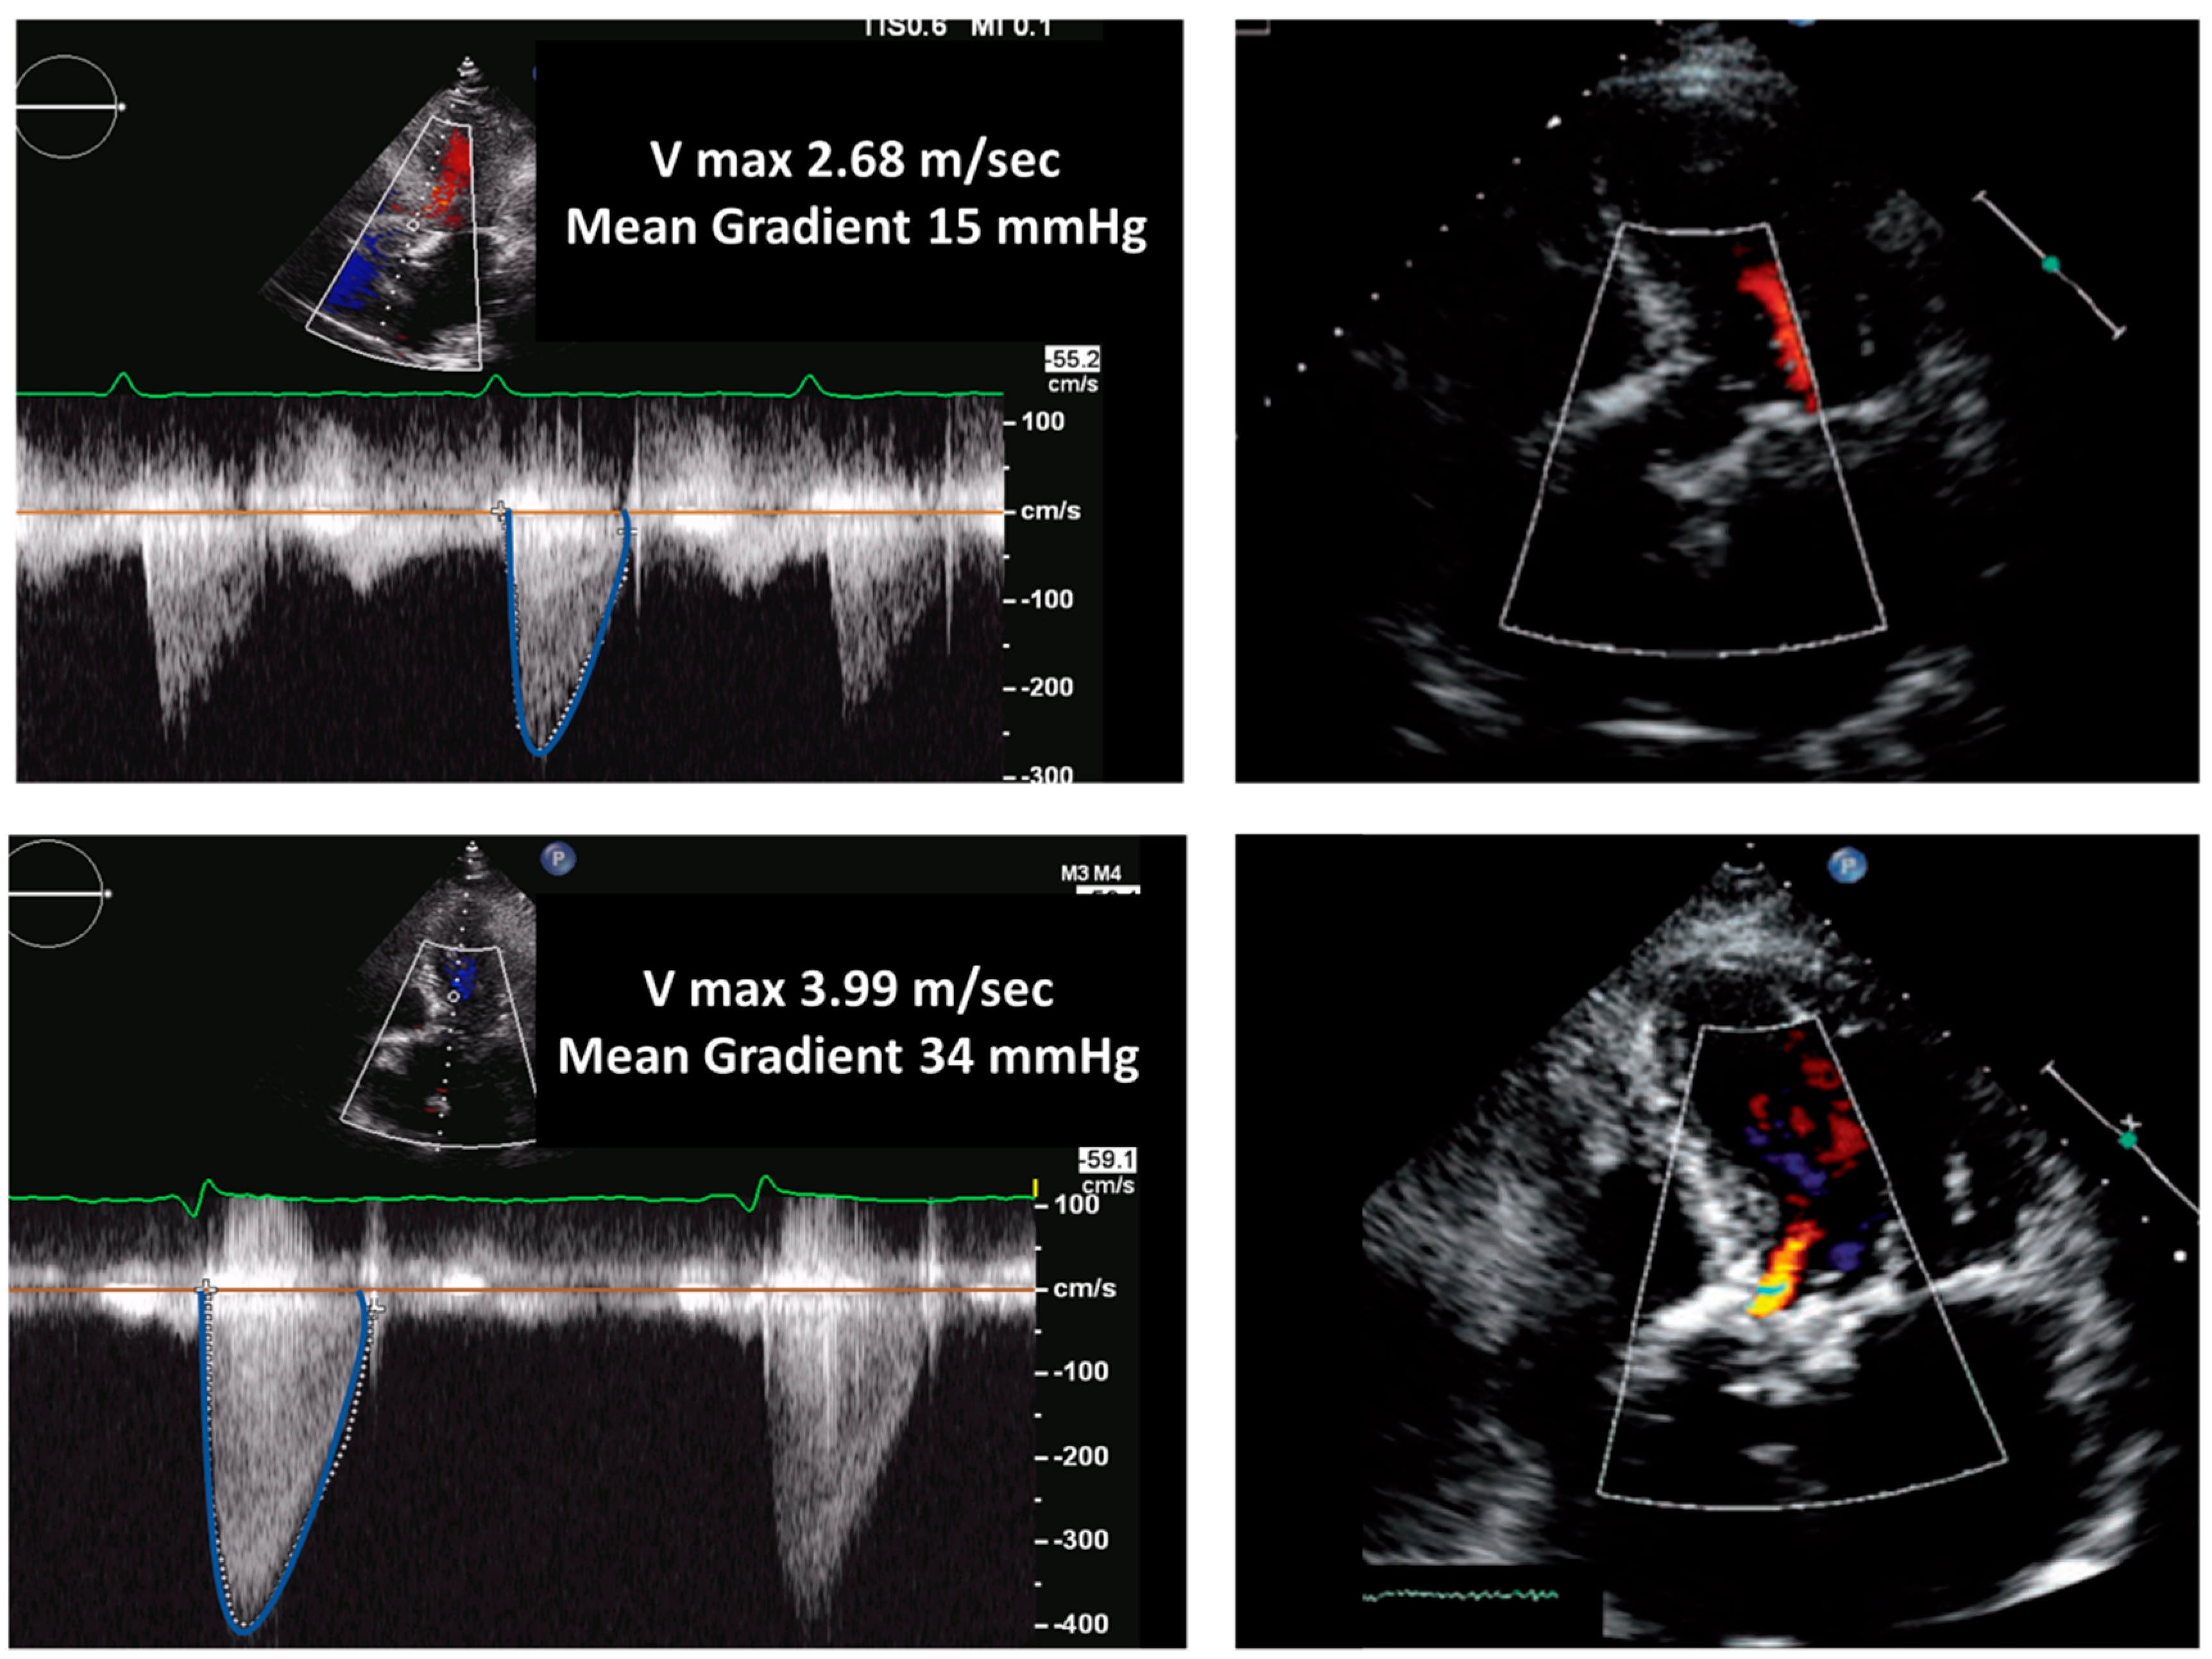

| TTE, TEE | Leaflet and/or ring thickening with diffuse or focal hyperechogenicity (calcifications). Reduced leaflet mobility. Leaflets’ fenestration, avulsion, or perforation. Stenosis or regurgitation. | Iso-hypoechogenic mass adherent to leaflets and ring, with leaflet thickening. Normal or reduced cusp mobility. More often, stenosis; regurgitation is uncommon. | Vegetations, diffuse or focal leaflets thickening, cusps perforation, wear or tear or cusp avulsion. Vegetation motion independent to cusps motion. Paravalvular complications: abscess, pseudo-aneurysm, fistula or dehiscence (and in some cases valve rocking) |

| SVD Stages | Aortic Valve Bioprosthesis | Mitral Valve Bioprosthesis |

|---|---|---|

| Stage 1 | Morphological valve deterioration without hemodynamic impairment. | Morphological valve deterioration without hemodynamic impairment. |

| Vmax: <3 m/s; Mean gradient < 20 mmHg, with an increase in mean gradient during follow-up < 10 mmHg; DVI > 0.35; AT < 100 ms; AT/ET < 0.32; EOA > 1.2 cm2 for BSA < 1.6 m2; EOA > 1 cm2 for BSA < 1.6 m2. | Mean gradient < 5 mmHg; DVI < 0.4; MVA > 1.5 cm2. | |

| Stage 2 | Morphological valve deterioration plus one of the following: | Morphological valve deterioration plus one of the following: |

| Vmax: 3–4 m/s; Mean gradient: 20–40 mmHg, with an increase in mean gradient during follow-up between 10 and 20 mmHg; DVI between 0.25 and 0.35; AT between 80 and 100 ms; AT/ET between 0.32 and 0.37; EOA between 1 and 1.2 cm2 for BSA < 1.6 m2; EOA between 0.8 and 1.1 cm2 for BSA > 1.6 m2; Moderate regurgitation. | Increase in DVI ≥ 0.4 or ≥20% resulting in DVI ≥ 2.2; Decrease in MVA ≥ 0.5 cm2 or ≥25% resulting in MVA < 1.5 cm2, compared with echocardiographic assessment performed post-surgery; Mean gradient > 5 mmHg; Moderate regurgitation. | |

| Stage 3 | Morphological valve deterioration plus one of the following: | Morphological valve deterioration plus one of the following: |

| Vmax > 4 m/s; Mean gradient > 40 mmHg, with an increase in mean gradient > 20 mmHg during follow-up; AT > 100 ms; AT/ET > 0.37; EOA < 1 cm2 for BSA < 1.6 m2; EOA < 0.8 cm2 for BSA > 1.6 m2. Severe regurgitation | Increase in DVI ≥ 0.8 or ≥ 40% resulting in DVI ≥ 2.5; Decrease in MVA ≥ 1.0 cm2 or ≥50% resulting in MVA < 1.0 cm2, compared to echocardiographic assessment performed post-surgery; Mean gradient > 10 mm Hg during follow-up; Severe regurgitation. |